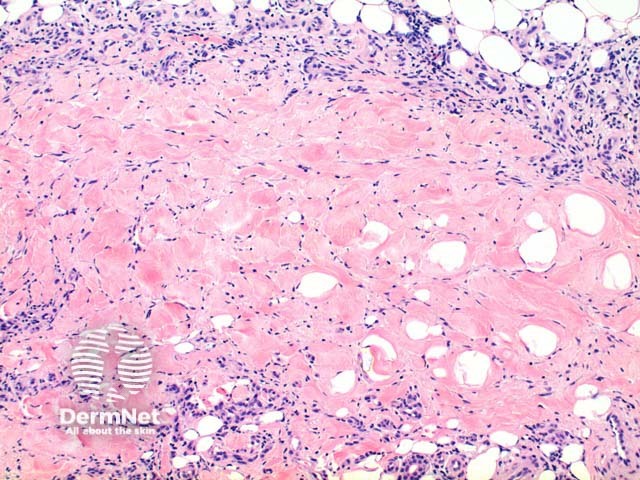

Scanning power view of necrobiosis lipoidica demonstrates a layered inflammatory process and alternating zones of necrobiosis involving the full thickness of the dermis (Figure 1). The changes tend to become more pronounced deeper in the dermis and may extend into the septal panniculus (Figures 2 and 3). The areas of necrobiosis are poorly defined and run into each other with broad foci of inflammatory infiltrate intervening (Figure 4). This may form a stacked ‘lasagne’ type appearance. A variable histiocytic infiltrate with multinucleated giant cells surrounds these areas. The accompanying inflammatory infiltrate is predominantly lymphocytic with plasma cells and occasional eosinophils (Figure 5). As lesions age an increasing degree of dermal fibrosis is seen.

Figure 2

Figure 3